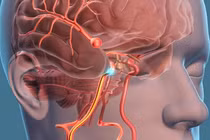

Túi phình mạch não là tình trạng thành động mạch não bị yếu và phồng lên tạo thành một túi nhỏ. Khi túi phình lớn dần, thành mạch trở nên mỏng và dễ vỡ.

Túi phình mạch máu não là tình trạng mạch máu trong não bị phình ra tại một ví trí nào đó. Khi bị vỡ, người bệnh phải đối mặt với những hậu quả nghiêm trọng đến tính mạng như đột quỵ xuất huyết não, động kinh...